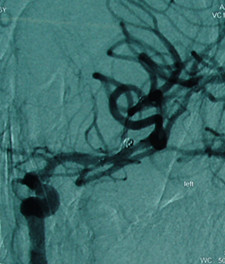

病例2:左侧大脑中动脉瘤术后           病例2:左侧大脑中动脉瘤术前

3例病人均为中年女性,均为突发头疼伴有意识障碍数小时入院,经CTA检查为宽颈动脉瘤,且瘤体不规则,介入栓塞技术要求较高,需术中支架辅助动脉瘤介入栓塞治疗。三例患者入院后,行积极术前准备。科室进行充分术前讨论。在吕正文主任指导下,由神经外科张明然、李庆民主治医师成功实施手术,手术过程顺利,术后病人恢复良好,无术中出血、血栓形成等并发症。

这三例手术成功实施,标志着泰安市中心医院神经外科介入水平进一步提高,达到省内先进水平,无论在介入手术的数量和质量上,在泰安市均处于领先地位。